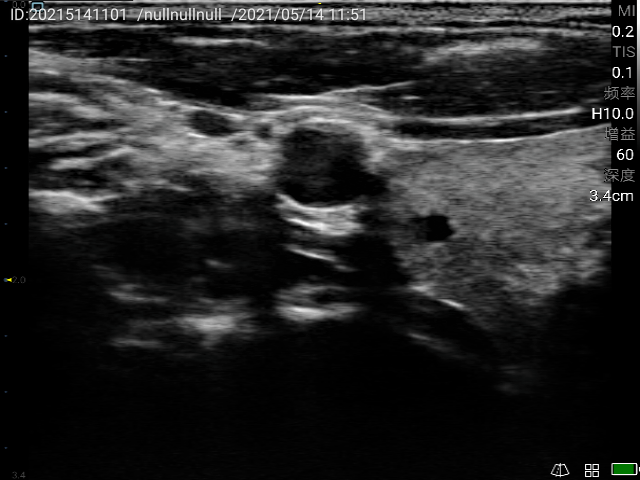

Accurate diagnosis of thyroid nodules and interventional guided puncture.

Breast and thyroid interventional ultrasound; Identify thyroid nodules and determine vascular lesions; Guide percutaneous biopsy to ensure accurate sampling; Guide fine needle aspiration to aspirate cysts.